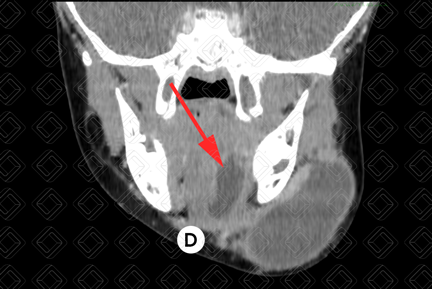

Texto alternativo para a imagem Figura 3. Créditos: Dra. Elazir Mota - Rio de Janeiro/RJ

Descrição das figuras 3, 4 e 5: Tomografia computadorizada do pescoço após administração do contraste venoso, evidenciando rânula mergulhante. Observe a formação cística (asteriscos) no espaço sublingual (seta vermelha) esquerdo, estendo para região submentoniana e submandibular deste lado devido à falha na musculatura milo-hioidea. Legenda: GH = gênio-hioideo; G = genioglosso; M = milo-hioideo; D = digástrico.

• Tomografia computadorizada do pescoço: Apresenta-se como cisto, bem definido e bem delimitado, homogêneo, com baixa atenuação central, com paredes finas e bem identificadas, que podem realçar pelo meio de contraste (figura 2).